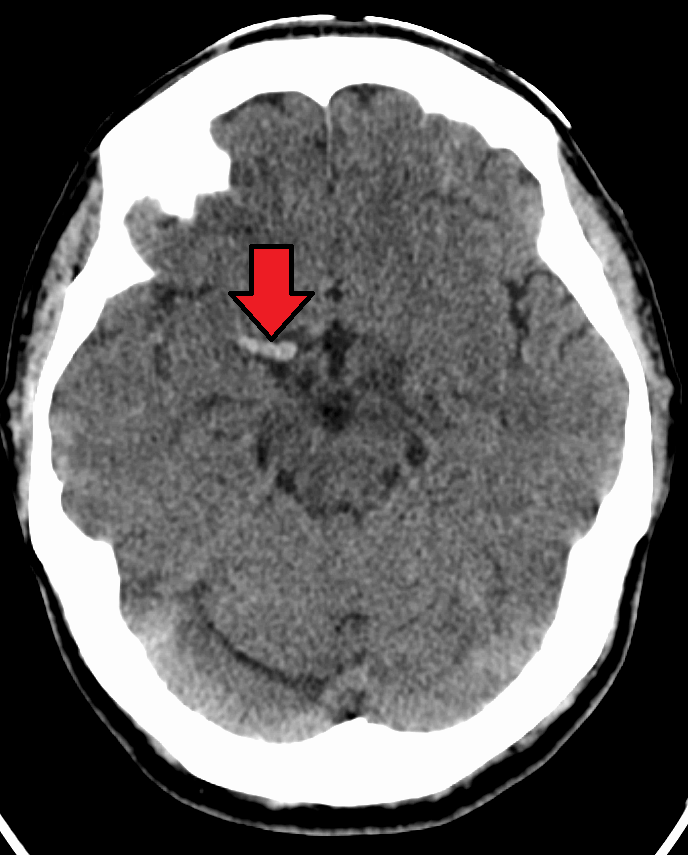

How does ischemic stroke appear on CT?

Hypodense (darker) compared to normal brain tissue.

What causes a hemorrhagic stroke?

Rupture of a weakened blood vessel.

How does acute hemorrhage appear on CT?

Hyperdense (bright/white).

Why is CTA not performed if hemorrhage is detected?

Contrast enhancement may be mistaken for active bleeding.

What is the first scan performed in a Hot Stroke protocol?

Non-contrast CT Head.

Why must non-contrast CT be performed first?

To rule out intracranial hemorrhage.

What must the technologist do if hemorrhage is seen?

Alert the radiologist and cancel the CTA.